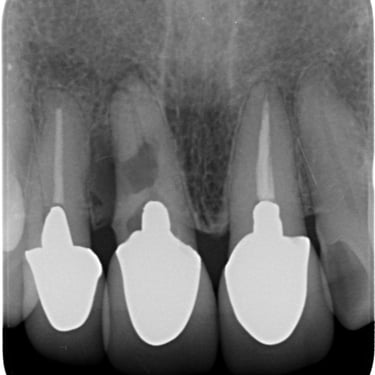

Hipercementosis

La hipercementosis es un engrosamiento anormal del cemento radicular del diente, a menudo debido a una inflamación crónica o trauma.

Los pacientes generalmente no tienen síntomas, pero la condición puede ser descubierta en una radiografía.

El tratamiento no suele ser necesario a menos que cause problemas con la extracción del diente.